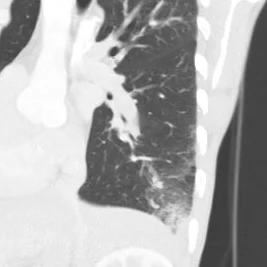

Conventional CT (oblique sagittal) shows normal appearing right lower lobe pulmonary artery

Oblique sagittal image lung windows shows infiltrate in the costophrenic angle with surrounding ground-glass opacity